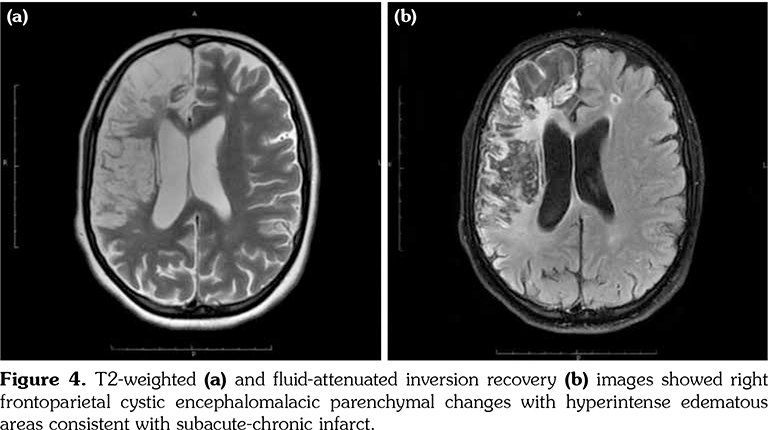

A 14-year-old female patient referred to our clinic with headache and dizziness for two weeks and loss of consciousness for about 10 minutes. On admission, the blood pressure was 90/60 mmHg and all peripheral pulses were palpable. Her body weight was above 97th percentile for her age and body mass index was 33. The fundus examination and other organ systems were essentially normal. Laboratory studies revealed erythrocyte sedimentation rate (ESR) as 108 mm/hour and C-reactive protein (CRP) as 7.5 mg/dL (0-0.8), while other measurements were normal. Urinalysis revealed microscopic hematuria and proteinuria of 31.9 mg/m2/hour in 24-hour urine collection. The cerebrospinal fluid examination showed no abnormalities. Cranial magnetic resonance imaging (MRI) showed multiple millimetric hyperintense deep white matter lesions on T2-weighted imaging (Figure 1). Intracranial and extracranial arteries were normal in magnetic resonance angiography (MRA). Renal biopsy findings were interpreted as FSGS (Figure 2). Patient was considered as cerebral vasculitis and incidental FSGS. Pulse methylprednisolone therapy for three consecutive days was initiated and continued with oral prednisolone. At four years of follow-up, proteinuria decreased to 5-15 mg/m2/hour, and ESR and CRP were normal. Repeated brain MRI and MRA examinations showed no new lesions. Four years later, at the age of 18, on a routine examination, both radial artery pulses were absent and the blood pressure could not be measured. Significant bruit was heard on the left carotid artery. Laboratory studies revealed ESR as 43 mm/hour and CRP as 2.46 mg/dL. Aortic MRA revealed diffuse wall thickening and contrast enhancement in the arcus aorta and its many main branches (Figure 3). Takayasu arteritis diagnosis was established according to the European League Against Rheumatism/ Paediatric Rheumatology International Trials Organisation/Paediatric Rheumatology European Society criteria.[2] Methotrexate was begun, and daily prednisolone was continued. Four months after the diagnosis of TA, left-sided hemiparesis developed. Brain MRI demonstrated a wide cerebral infarct at the right anterior vascular territory (Figure 4). Brain and neck computed tomography angiography showed total occlusion of the right internal carotid artery. Vascular involvement of the right common carotid artery was progressed to preocclusive stenosis. Diameters of the right anterior and middle cerebral arteries were thin and fed by the posterior and anterior communicating arteries (Figure 5). Tocilizumab treatment was started at 8 mg/kg every four weeks. At follow- up with 2.5 years of tocilizumab treatment, the patient's clinical condition improved slightly, and no new symptoms developed. A written informed consent was obtained from the patient.

Several causes of ischemic stroke in patients with TA have been described, including embolism from stenotic or occlusive lesions in the aortic arch and its main branches or cardiac diseases.[6] In addition, intracranial stenosis have been observed as a consequence of vasculitic involvement or a prior embolization into the vessel. In our patient, based on the MRI scan, this cerebral accident seemed to be a vascular occlusion.